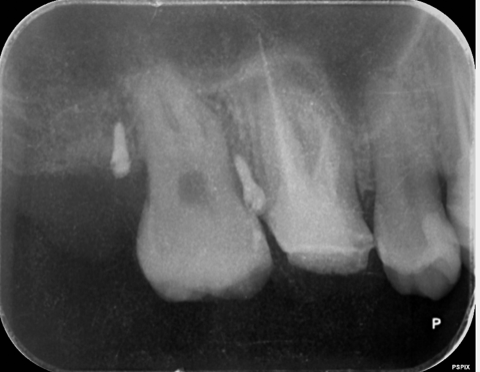

【池袋 歯医者】歯を抜かずに救う“最後の一手”──AT...

【池袋 歯医者】歯根嚢胞に対する歯根端切除術とは...

[池袋 歯医者]その歯、まだ残せるかもしれません